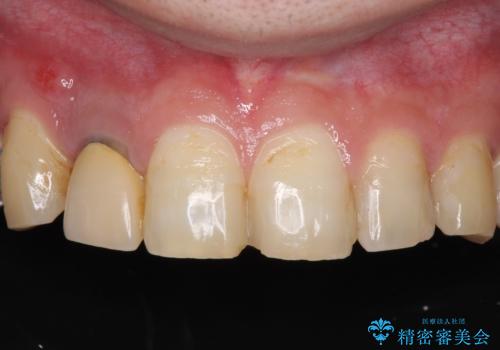

折れてしまった前歯 インプラントによる補綴治療